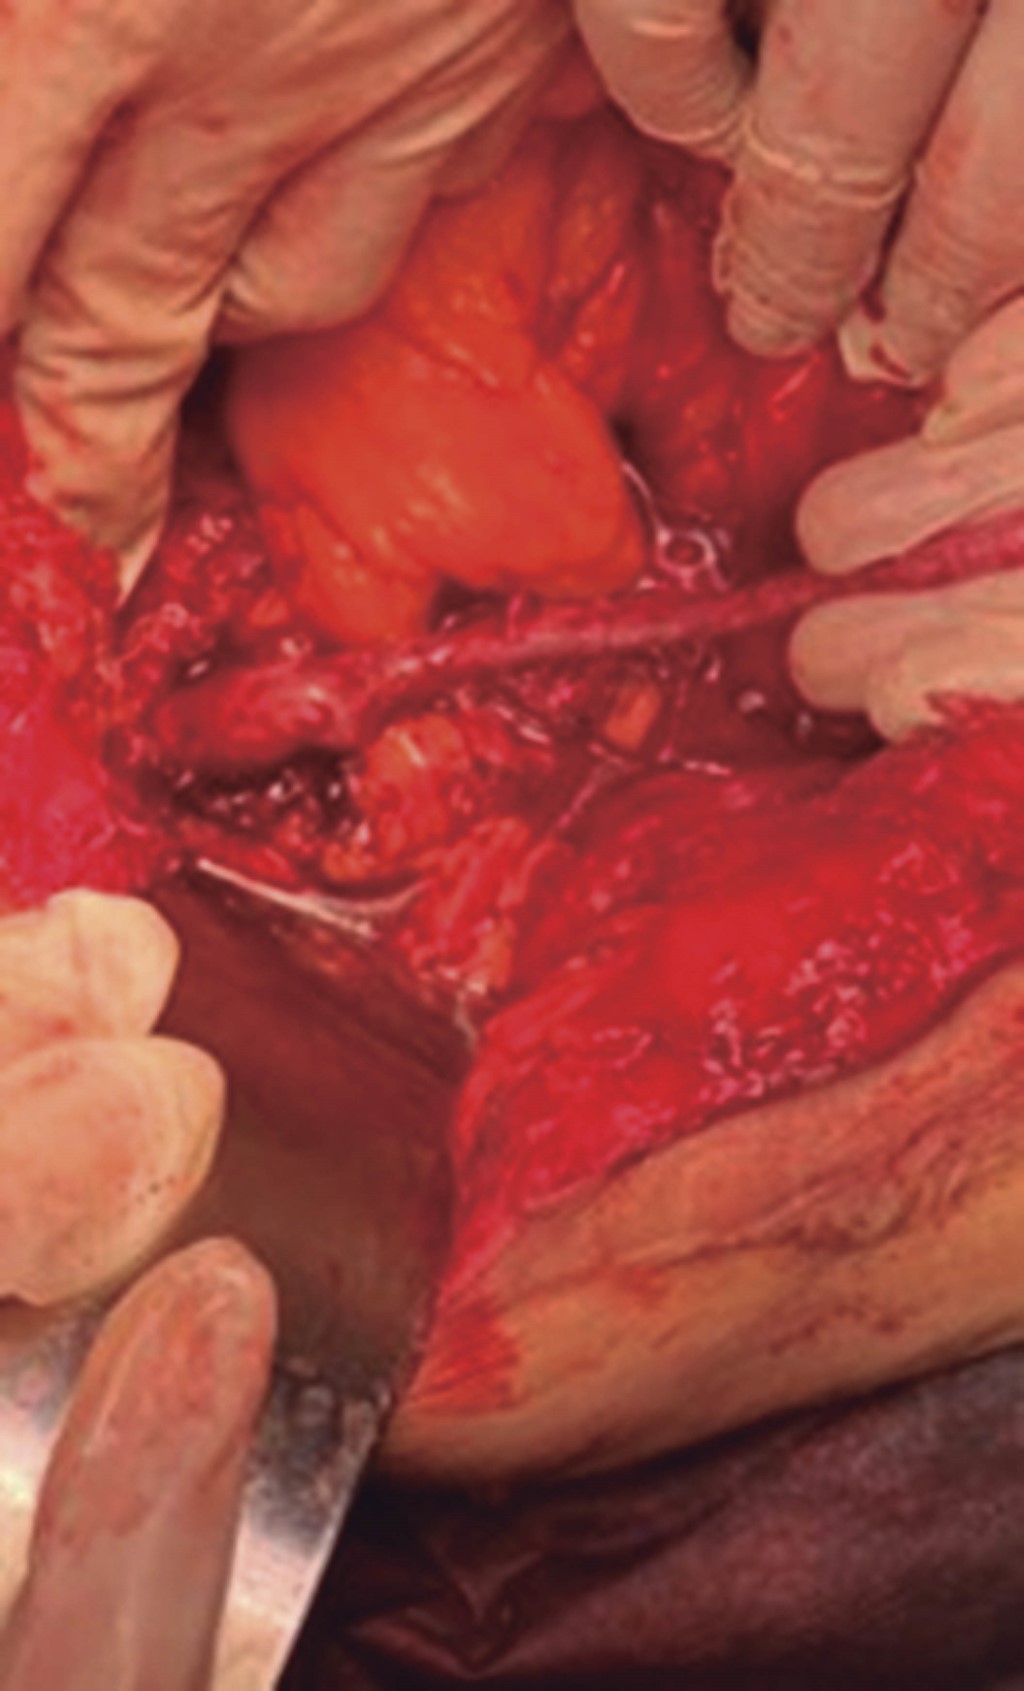

Figure 2